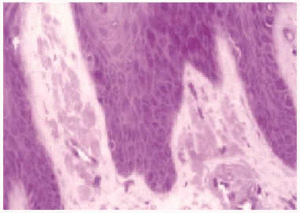

Una biopsia de la lesión cutánea mostró en la tinción con hematoxilina-eosina (fig. 2), un epitelio con una zona de intensa hiperqueratosis, acantosis y papilomatosis con algún cuerpo coloide aislado. En dermis papilar se observaron pequeños depósitos, bien delimitados de una sustancia amorfa, acidófila que daba reacción metacromática con el cristal violeta (fig. 3) y era positiva para rojo Congo (fig. 4). En esa misma zona se observaron incontinencia de pigmento.

Fig. 3.--Depósitos papilares que dan reacción metacromática con el cristal violeta.